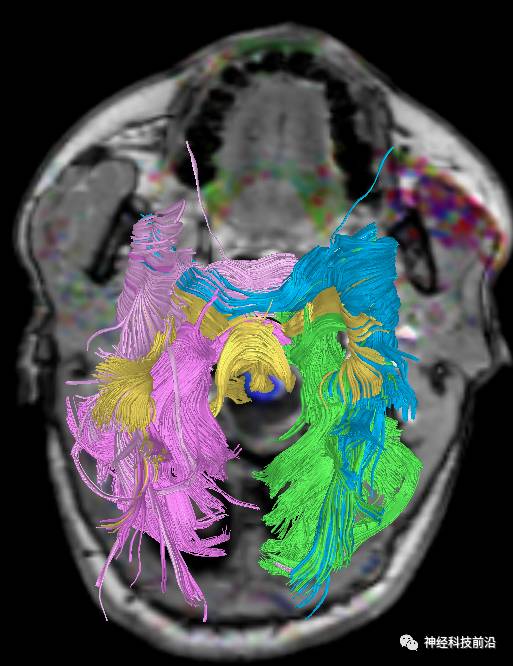

下面为皮质脑桥束的走形方位

皮质脑桥束与脑干高信号(黄色)纤维束

上述纤维束与小脑中脚的位置毗邻